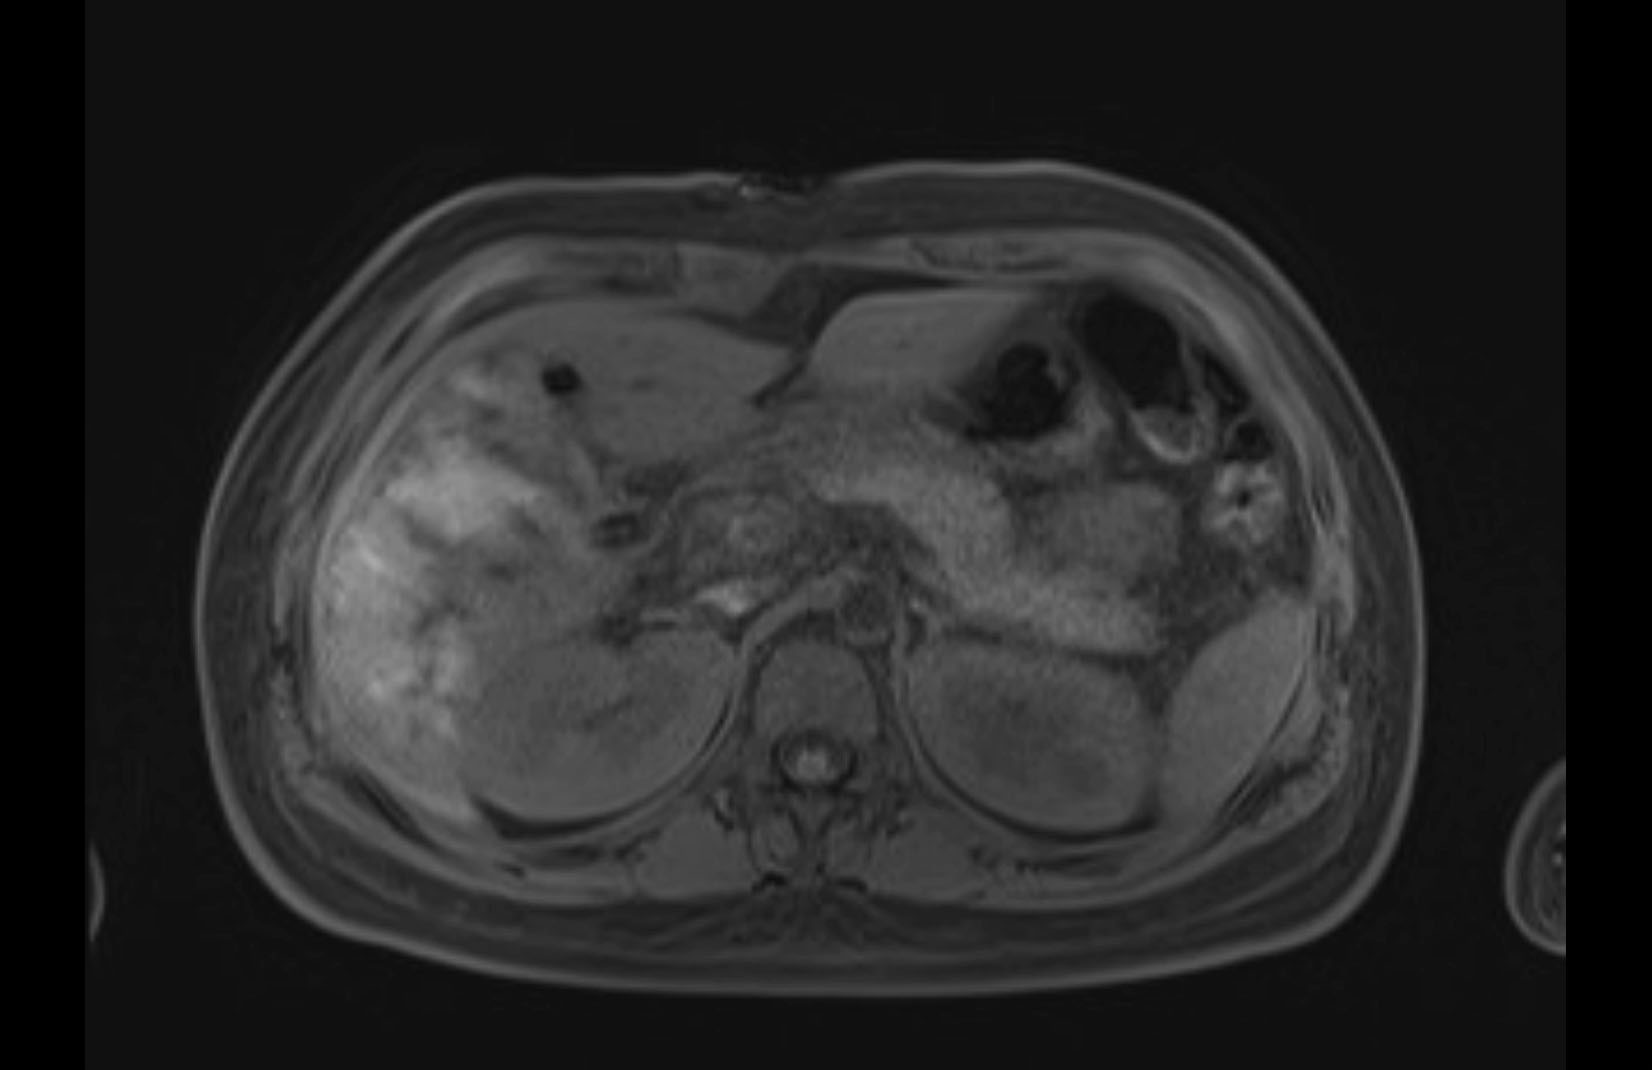

MRI T1

MRI T2